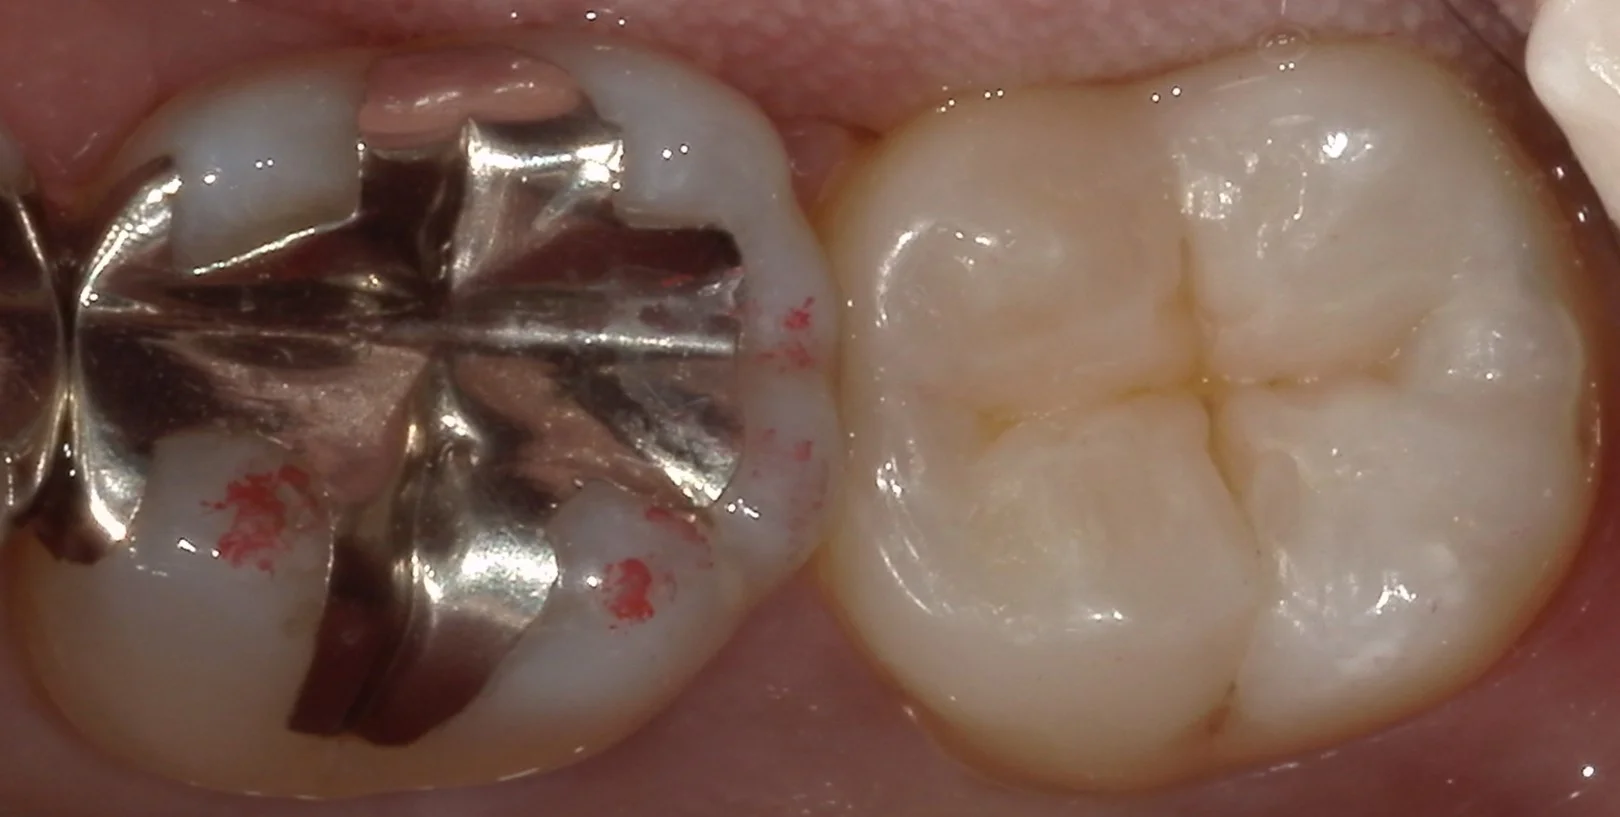

そして、詰め終わったのがこちらです。

実は小さい虫歯ほどその形態を付与するのは難しいのですが、うまいこと付与できたかと思います。

時間がかかった分、歯が乾燥して色があっていない箇所もありますが、1週間もすれば歯に水分が戻り、色は馴染んでくるはずです。

これだけ歯がしっかりと残っている状態なので、非常に長期的な予後が期待できると思いますので、私もその予後を追うのが楽しみですね。